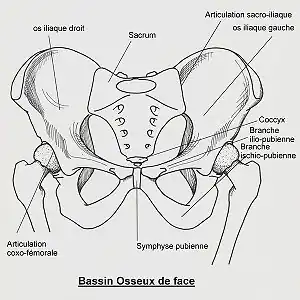

En anatomie le bassin osseux (en latin pelvis) est une partie du squelette humain, en forme d'entonnoir, constitué des deux os coxaux latéraux, du coccyx et du sacrum en arrière. Il constitue la limite squelettique de la cavité pelvienne et de la ceinture pelvienne.

Le bassin est constitué de plusieurs éléments :

- un élément central et postérieur : la partie caudale de la colonne vertébrale fixe constituée du sacrum et du coccyx ;

- deux os pairs et symétriques : les os coxaux. Ils sont chacun constitués de trois os qui se soudent entre eux vers l'âge de 12 ans. Cette soudure forme un Y au niveau de la fosse acétabulaire. Ces trois os sont :

- l'ilium est la partie supérieure (haute) de la soudure en forme de Y, c'est ce que l'on appelle communément la hanche ;

- l'ischium est la partie inféro-dorsale (basse dirigée en arrière) de la soudure en forme de Y, la partie la plus basse de l'ischium est la tubérosité ischiatique (c'est l'os sur lequel on s'assoit) ;

- le pubis est la partie inféro-ventrale (basse dirigée en avant) de la soudure en forme de Y, c'est la partie osseuse située au-dessus du sexe, ou bien l'endroit où se situent les poils pubiens, chez l'adulte ;

L'ischium et les branches ischio-pubienne et supérieure du pubis forme un orifice osseux : le foramen obturé.

L'ilium forme une grande aile : l'aile iliaque.

L'épine ischiatique délimite deux ouvertures : la grande incisure ischiatique et la petite incisure ischiatique.

Les deux os coxaux sont unis :

- au sacrum par les deux articulations sacro-iliaques en arrière ;

- entre eux par la symphyse pubienne en avant qui n'a qu'une petite possibilité de mouvement (quelques millimètres) pour amortir les mouvements de la marche.

Il donne attache sur les côtés aux membres inférieurs par les articulations coxo-fémorales (hanche) entre le cotyle et la tête fémorale. Cette articulation se fait via une cavité articulaire située au centre de l'os coxal : l'acétabulum qui reçoit la tête fémorale.